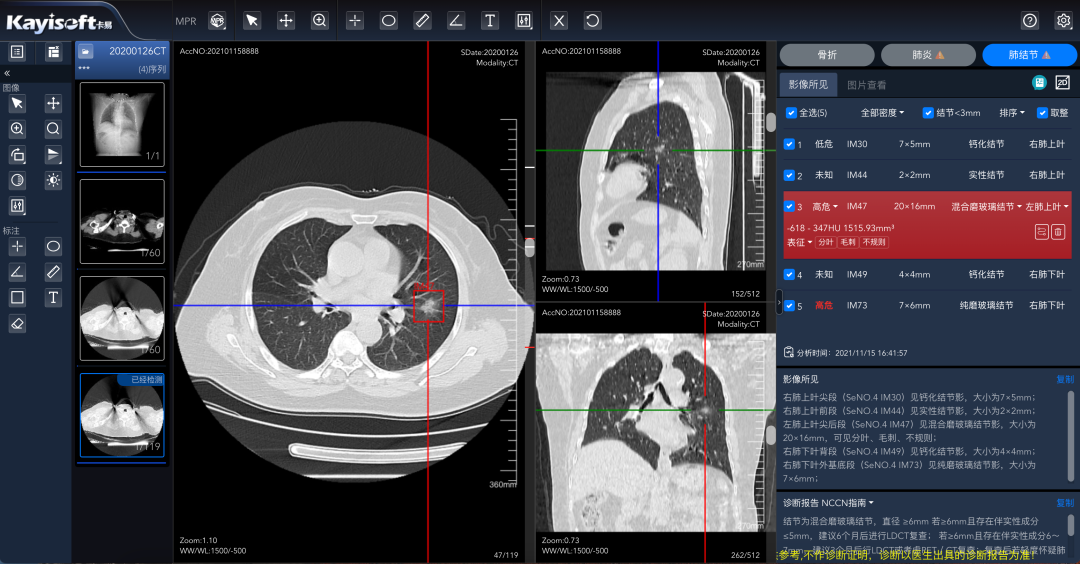

¡®¿µ½¡ÔƼ졯ƽ̨µÄÁÁµãÔÚÓÚÆäǿʢµÄAIÖÇÄÜÕï¶Ï¹¦Ð§¡£¡£ ¡£¡£¡£¡£¡£¸Ãƽ̨Äܹ»×Ô¶¯Ê¶±ðÓ°Ïñ£¬£¬ £¬ £¬ £¬Ìṩ²¡ÔîÖÇÄÜÕï¶ÏÆÊÎö£¬£¬ £¬ £¬ £¬²¢ÌìÉúͼÎĽṹ»¯±¨¸æ¡£¡£ ¡£¡£¡£¡£¡£Ïà½ÏÓڹŰåµÄÈ˹¤Á÷³Ì£¬£¬ £¬ £¬ £¬Õâһϵͳ²»µ«ÄܽÚÔ¼´ó×Úʱ¼ä£¬£¬ £¬ £¬ £¬Ìá¸ßЧÂÊ£¬£¬ £¬ £¬ £¬»¹ÄÜÔÚÒ»¶¨Ë®Æ½ÉϱÜÃ⩼ìºÍÎóÕïµÄ±¬·¢¡£¡£ ¡£¡£¡£¡£¡£ÓÉ´Ë£¬£¬ £¬ £¬ £¬Ò½ÁÆ×ÊÔ´Äܹ»ÊµÏÖ¼¯Öй²ÏíºÍ¸ßЧÉèÖ㬣¬ £¬ £¬ £¬Èû¼ÕßµÃÒÔÏíÊܼÒÃſڵġ°AI+¡±¿µ½¡ÊØ»¤¡£¡£ ¡£¡£¡£¡£¡£

»ùÓÚÇøÓòÓ°ÏñÔÆµÄCT·Î½á½ÚAIÆÊÎö

ÕâÒ»Ó¦ÓÃͨ¹ýÓ°ÏñÊý¾ÝÔÆ»¯ÖÎÀíÊý¾ÝͳһÊÕÂÞ£¬£¬ £¬ £¬ £¬ÊµÏÖÒÔÊý¾ÝΪ»ù´¡£¬£¬ £¬ £¬ £¬ÍŽá AI ÆÊÎöЧÀÍ£¬£¬ £¬ £¬ £¬ÊµÏַνá½ÚÖÇÄܱê×¢£¬£¬ £¬ £¬ £¬½µµÍ©Õï¡¢ÎóÕïµÄ¸ÅÂÊ£¬£¬ £¬ £¬ £¬½«ÕïÆ¬Ê±¼ä´Ó¹Å°åµÄ5·ÖÖÓ£¬£¬ £¬ £¬ £¬Ëõ¶Ìµ½ÁË2-3·ÖÖÓ¡£¡£ ¡£¡£¡£¡£¡£

640.png